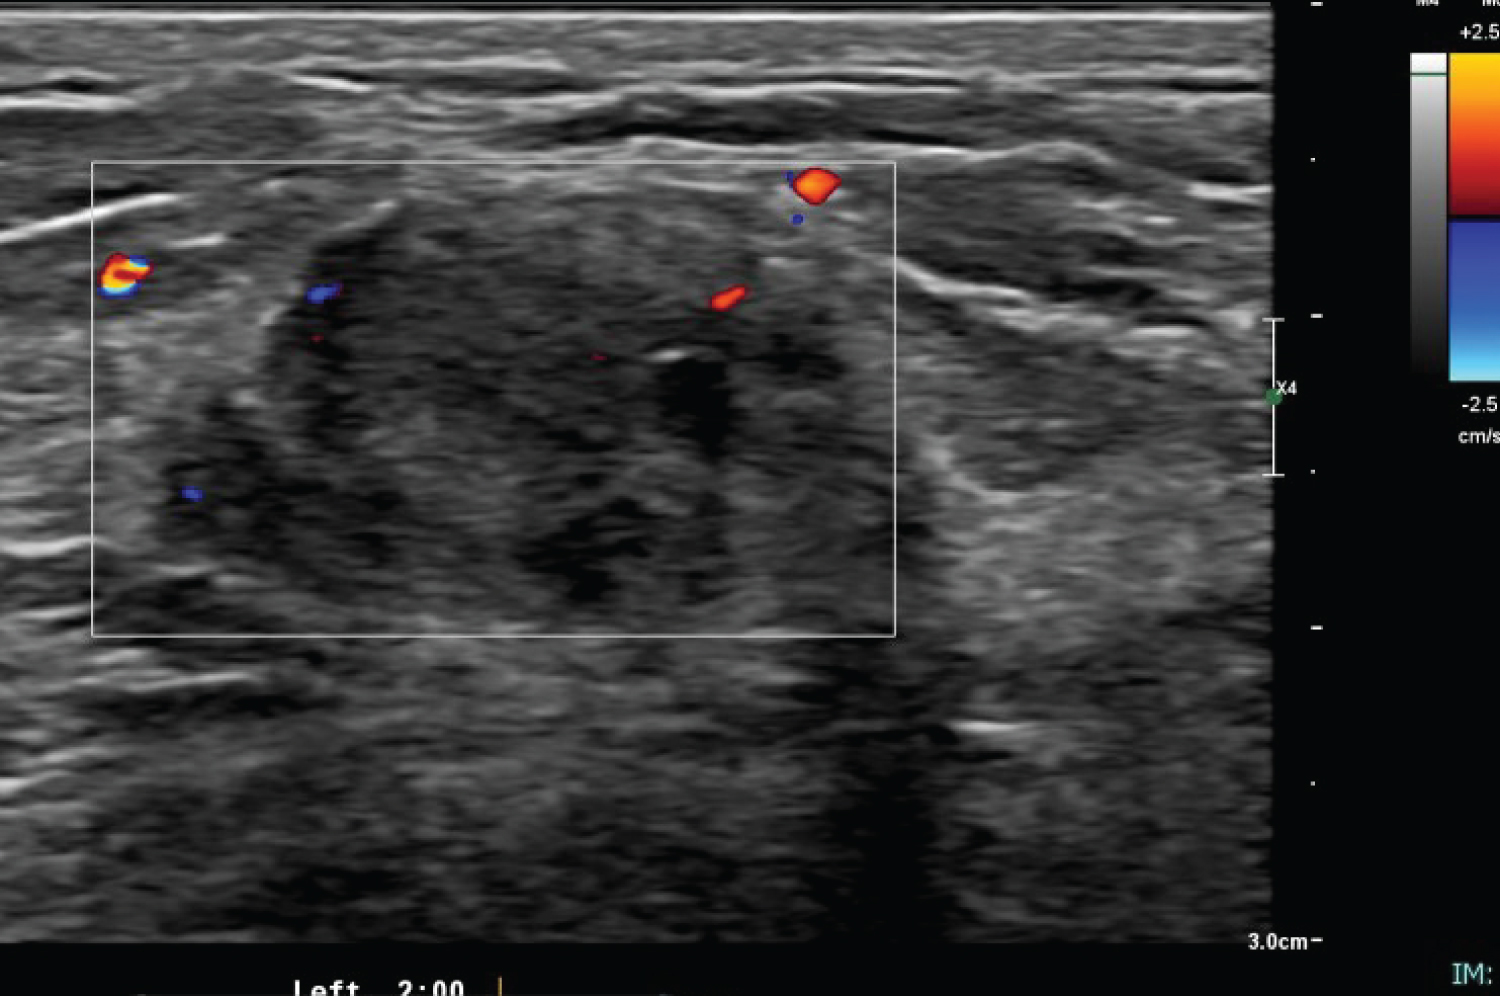

The ultrasound assessment of left breast showed 2.3 × 0.4 × 2.2 cm mass at 2 o'clock (Figure 3). It was irregular with heterogeneous echotexture. Some of the borders were indistinct. It has peripheral vascularity. The axillary lymph nodes were sonographically normal. The given BI-RADS were 5. For which ultrasound guided biopsy was done. The pathology revealed spindle cell lesion suspicious for fibromatosis with additional presence of rare atypical epithelial cells (Figure 4). The patient subsequently underwent wide local excision of the lesion with uneventful postoperative course. The patient subsequently underwent wide local excision of the lesion with uneventful postoperative course. Final histopathology was reported as Fibromatosis. The patient has been on regular follow up now for six months with no apparent local recurrence.

Figure 3: Ultrasound of left breast showing an irregular hypoechoic mass with indistinct margins seen at 2 o'clock. There associated mixed posterior features with peripheral vascularity. View Figure 3